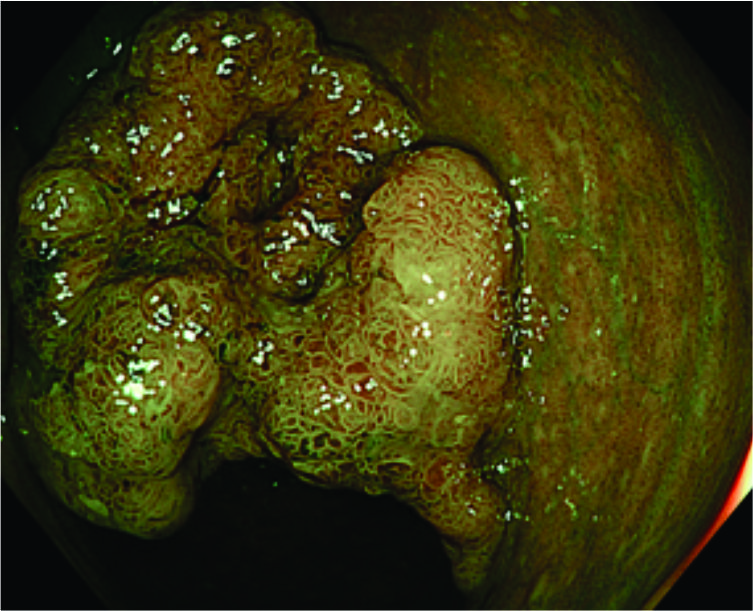

Pictures of large colon polyps, its endoscopic removal and the resection specimen

Endoscopic mucosal resection

• EMR is used to remove large polyps, usually those over 15-20 millimeters.

• After finding the polyp, a special dye solution is injected under it to lift it away from the deeper tissues.

• The doctor then uses a tool called a snare to safely remove the polyp.